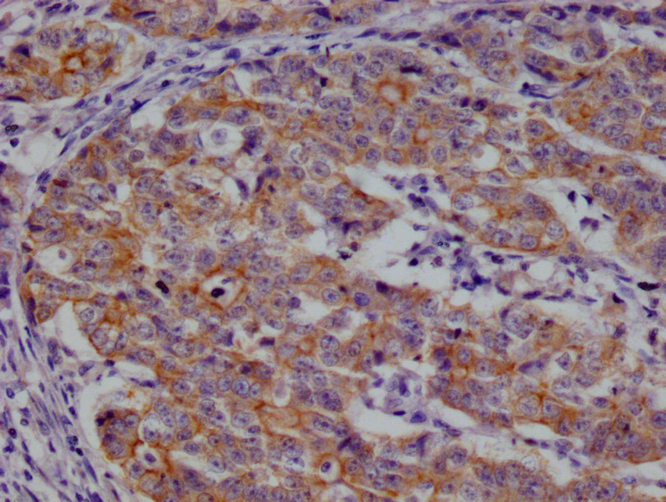

IHC image of CSB-RA959139A0HU diluted at 1:100 and staining in paraffin-embedded human colon cancer performed on a Leica BondTM system. After dewaxing and hydration, antigen retrieval was mediated by high pressure in a citrate buffer (pH 6.0). Section was blocked with 10% normal goat serum 30min at RT. Then primary antibody (1% BSA) was incubated at 4°C overnight. The primary is detected by a Goat anti-rabbit polymer IgG labeled by HRP and visualized using 0.05% DAB.

IHC image of CSB-RA959139A0HU diluted at 1:100 and staining in paraffin-embedded human prostate cancer performed on a Leica BondTM system. After dewaxing and hydration, antigen retrieval was mediated by high pressure in a citrate buffer (pH 6.0). Section was blocked with 10% normal goat serum 30min at RT. Then primary antibody (1% BSA) was incubated at 4°C overnight. The primary is detected by a Goat anti-rabbit polymer IgG labeled by HRP and visualized using 0.05% DAB.